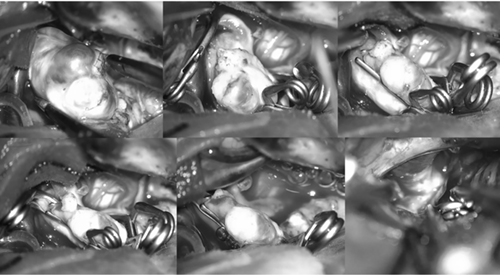

1月11日,在麻醉手术科等科室的配合下,杨伟副主任医师带领神经外科团队共同为患者实施了左侧翼点入路双侧复杂颅内动脉瘤夹闭术。历时4个多小时的“奋战”,经一侧切口入路成功夹闭了双侧2枚难度极高的动脉瘤,术中未发生动脉瘤提前破裂,穿支血管得到良好保护,运动诱发电位监测显示患者上下肢运动功能正常,术中荧光造影显示动脉瘤无显影,载瘤动脉及分支通畅;术后患者一般状况良好,无任何神经功能障碍,复查CT未见术区出血、脑组织缺血等异常表现。